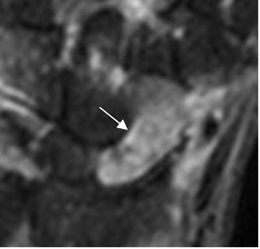

Fig 47. Contusión del escafoides.

RM coronal en STIR. Hueso escafoides hiperintenso, por contusión ósea. Hay fisura en la parte inferior. (Flecha).